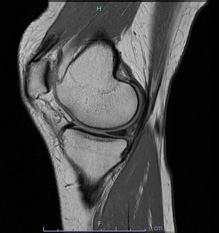

• 画像:損傷後内側半月板MRI画像(側面)

損傷後内側半月板MRI画像(側面)

• 画像:損傷後内側半月板MRI画像(正面)

損傷後内側半月板MRI画像(正面)